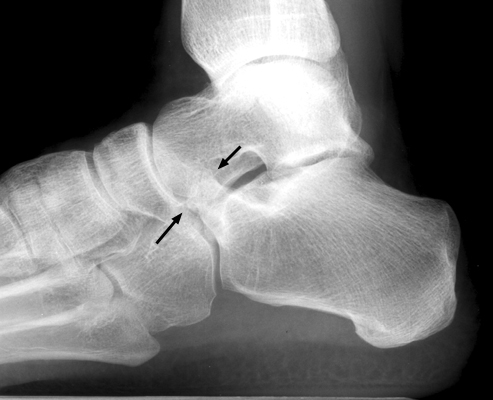

Calcaneonavicular coalition

Plain film and CT images of calcaneonavicular coalition. Notice the elongated, tubular like extension of the anterior calcaneus seen on the lateral film; this imagery has been likened to the elongated nose of an anteater. There is abnormal bony fusion of the calcaneus and navicular bones, with the presence of a bony bar extending between these two bones.